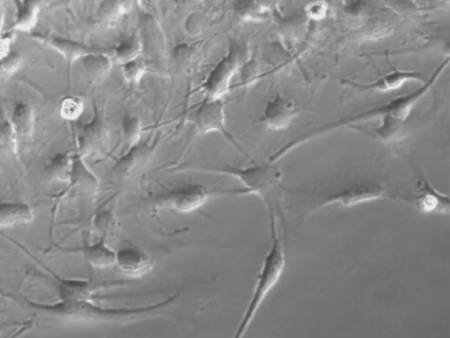

Células del tumor en cultivo. (Foto: DICYT)

El segundo aspecto relevante de esta publicación es que los investigadores demuestran también que el péptido reduce la movilidad de las células tumorales. Este factor es muy importante porque las células del glioma se dispersan por el cerebro con una gran facilidad, de manera que a veces extirpar el tumor mediante cirugía no sirve para acabar con él. Por eso, es uno de los tumores cerebrales con más baja esperanza de vida. Si el péptido patentado también consigue reducir esa movilidad, tal y como han comprobado los investigadores en cultivos celulares, sería otra razón para apostar por este agente terapéutico.